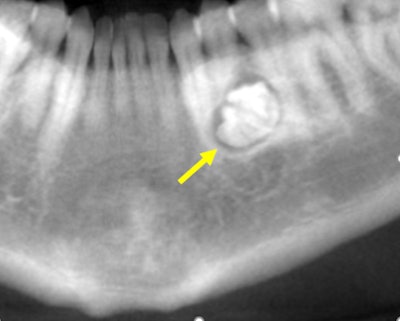

Figure 1: Reformatted CBCT panoramic film.

History: The patient is a 32-year-old woman who was referred to the oral surgeon by her dentist because of a lesion on the left mandible, which was noted in a panoramic film. The patient was asymptomatic and had no paresthesia or swelling.

Her past medical history was significant for seasonal allergies. The intraoral and extraoral exams were within normal limits.

The oral surgeon ordered a cone-beam computed tomography (CBCT) scan and requested an interpretation report by an oral radiologist. Images are provided below in the following order:

A hyperdense lesion (radiopaque) surrounded by a hypodense ring with very well-defined

borders. A distal extension of the lesion takes the form of a primitive root. The lesion is in the middle of the mandible. Tooth #21 is slightly mesially displaced. Initial resorption is observed at the distal third aspect of the root of tooth #21. The lesion is displacing apically the mental foramen.